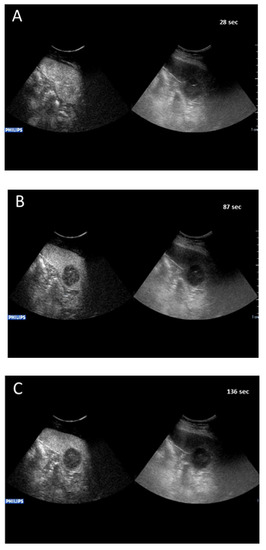

2.2.2. Splenic CEUS Patterns

2.2.3. Splenic CEUS Test Positivity